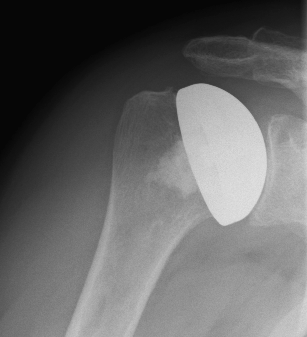

Special prostheses such as an inverse shoulder prosthesis (syn.: "Delta prosthesis", "Grammont prosthesis") for the combination of severe omarthrosis with joint instability and rotator cuff defects

Right: radiograph of an inverse shoulder prosthesis for rotator cuff defect arthropathy.

left: Inverted shoulder prosthesis (Aequalis reversed type, Tornier company).